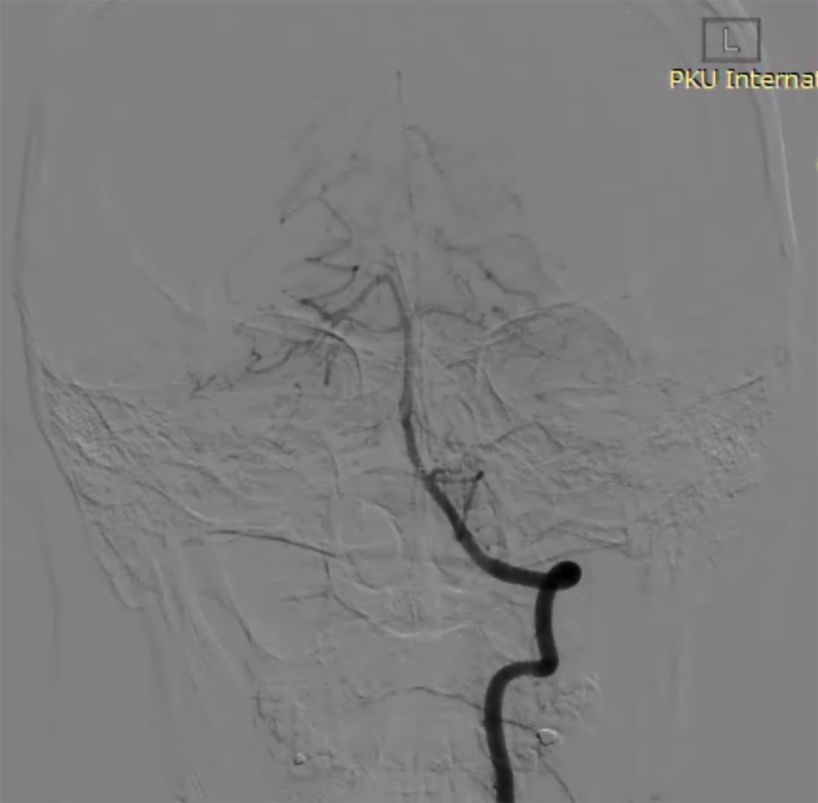

术后复查影像(图11)。

图11

本例介入手术共使用4枚长密网支架桥接放置治疗巨大长夹层动脉瘤,手术顺利,术中清晰可见支架桥接与放置打开情况,微创介入手术大约一个多小时,术后三天患者无任何后遗症步行出院,患者术后半年CTA血管造影复查,脑动脉瘤顽疾得以治愈,脑血管形态已经基本恢复正常 ,患者恢复良好,生活完全正常并重返工作岗位。

术后患者生命体征平稳,视力视野较术前无明显变化,肢体感觉及运动较术前无明显变化。